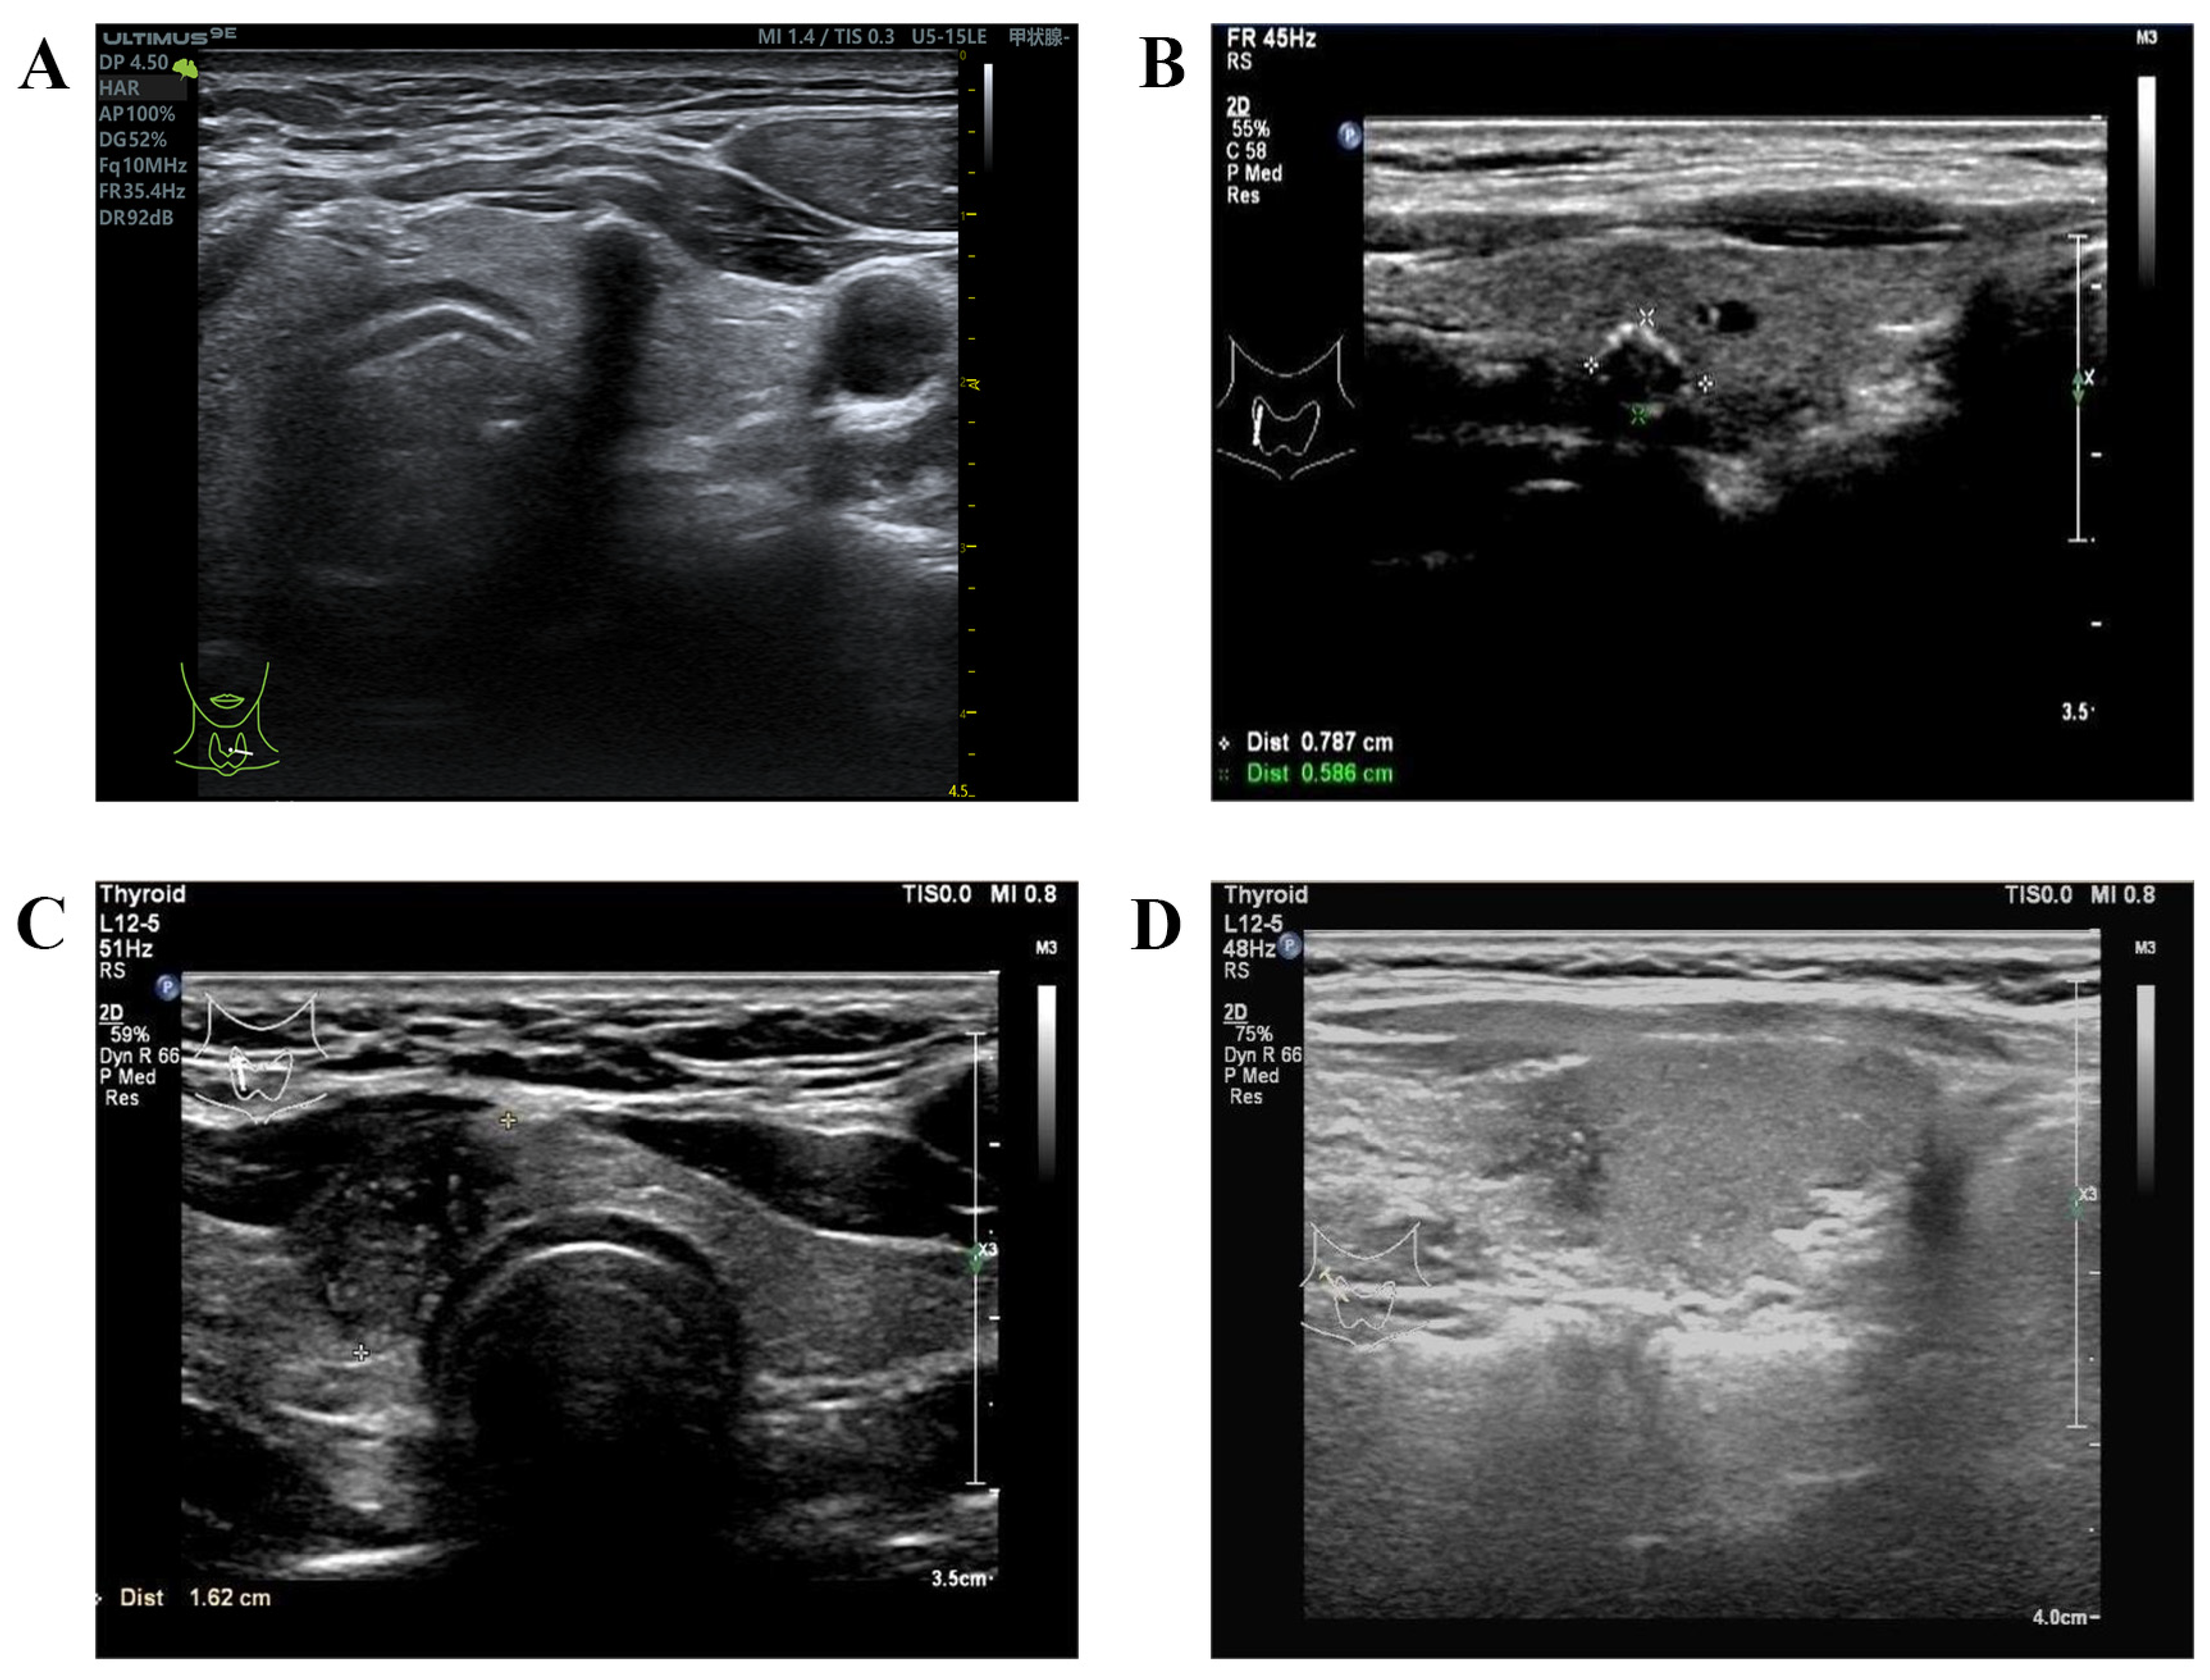

3. Conventional Gray-Scale and Doppler US

4.1. CEUS

4.2. SWE